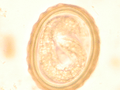

The larva of Ascaris lumbricoides developing in the egg

Ascaris egg, incubation process: The ascaris egg incubation process consists in placing the egg in a controlled environment, at 26°C during 28 days, in acidic conditions. This process allows to evaluate if an egg is viable or not, by watching the bipartition of the nucleus, and the growth of the larva.

The diagnosis is usually incidental when the host passes a worm in the stool or vomit. The eggs can be seen in smear of fresh feces examined on a glass slide under a microscope and there are various techniques to concentrate them first or increase their visibility, such as the ether sedimentation method or the Kato technique. The eggs have a characteristic shape: they are oval with a thick, mamillated shell (covered with rounded mounds or lumps), measuring 35-50 micrometer in diameter and 40-70 in length. During pulmonary disease larvae may be found in fluids aspirated from the lungs. White blood cells counts may demonstrate peripheral eosinophilia; this is common in many parasitic infections and is not specific to ascariasis. On X-ray, 15–35 cm long filling defects, sometimes with whirled appearance (bolus of worms).